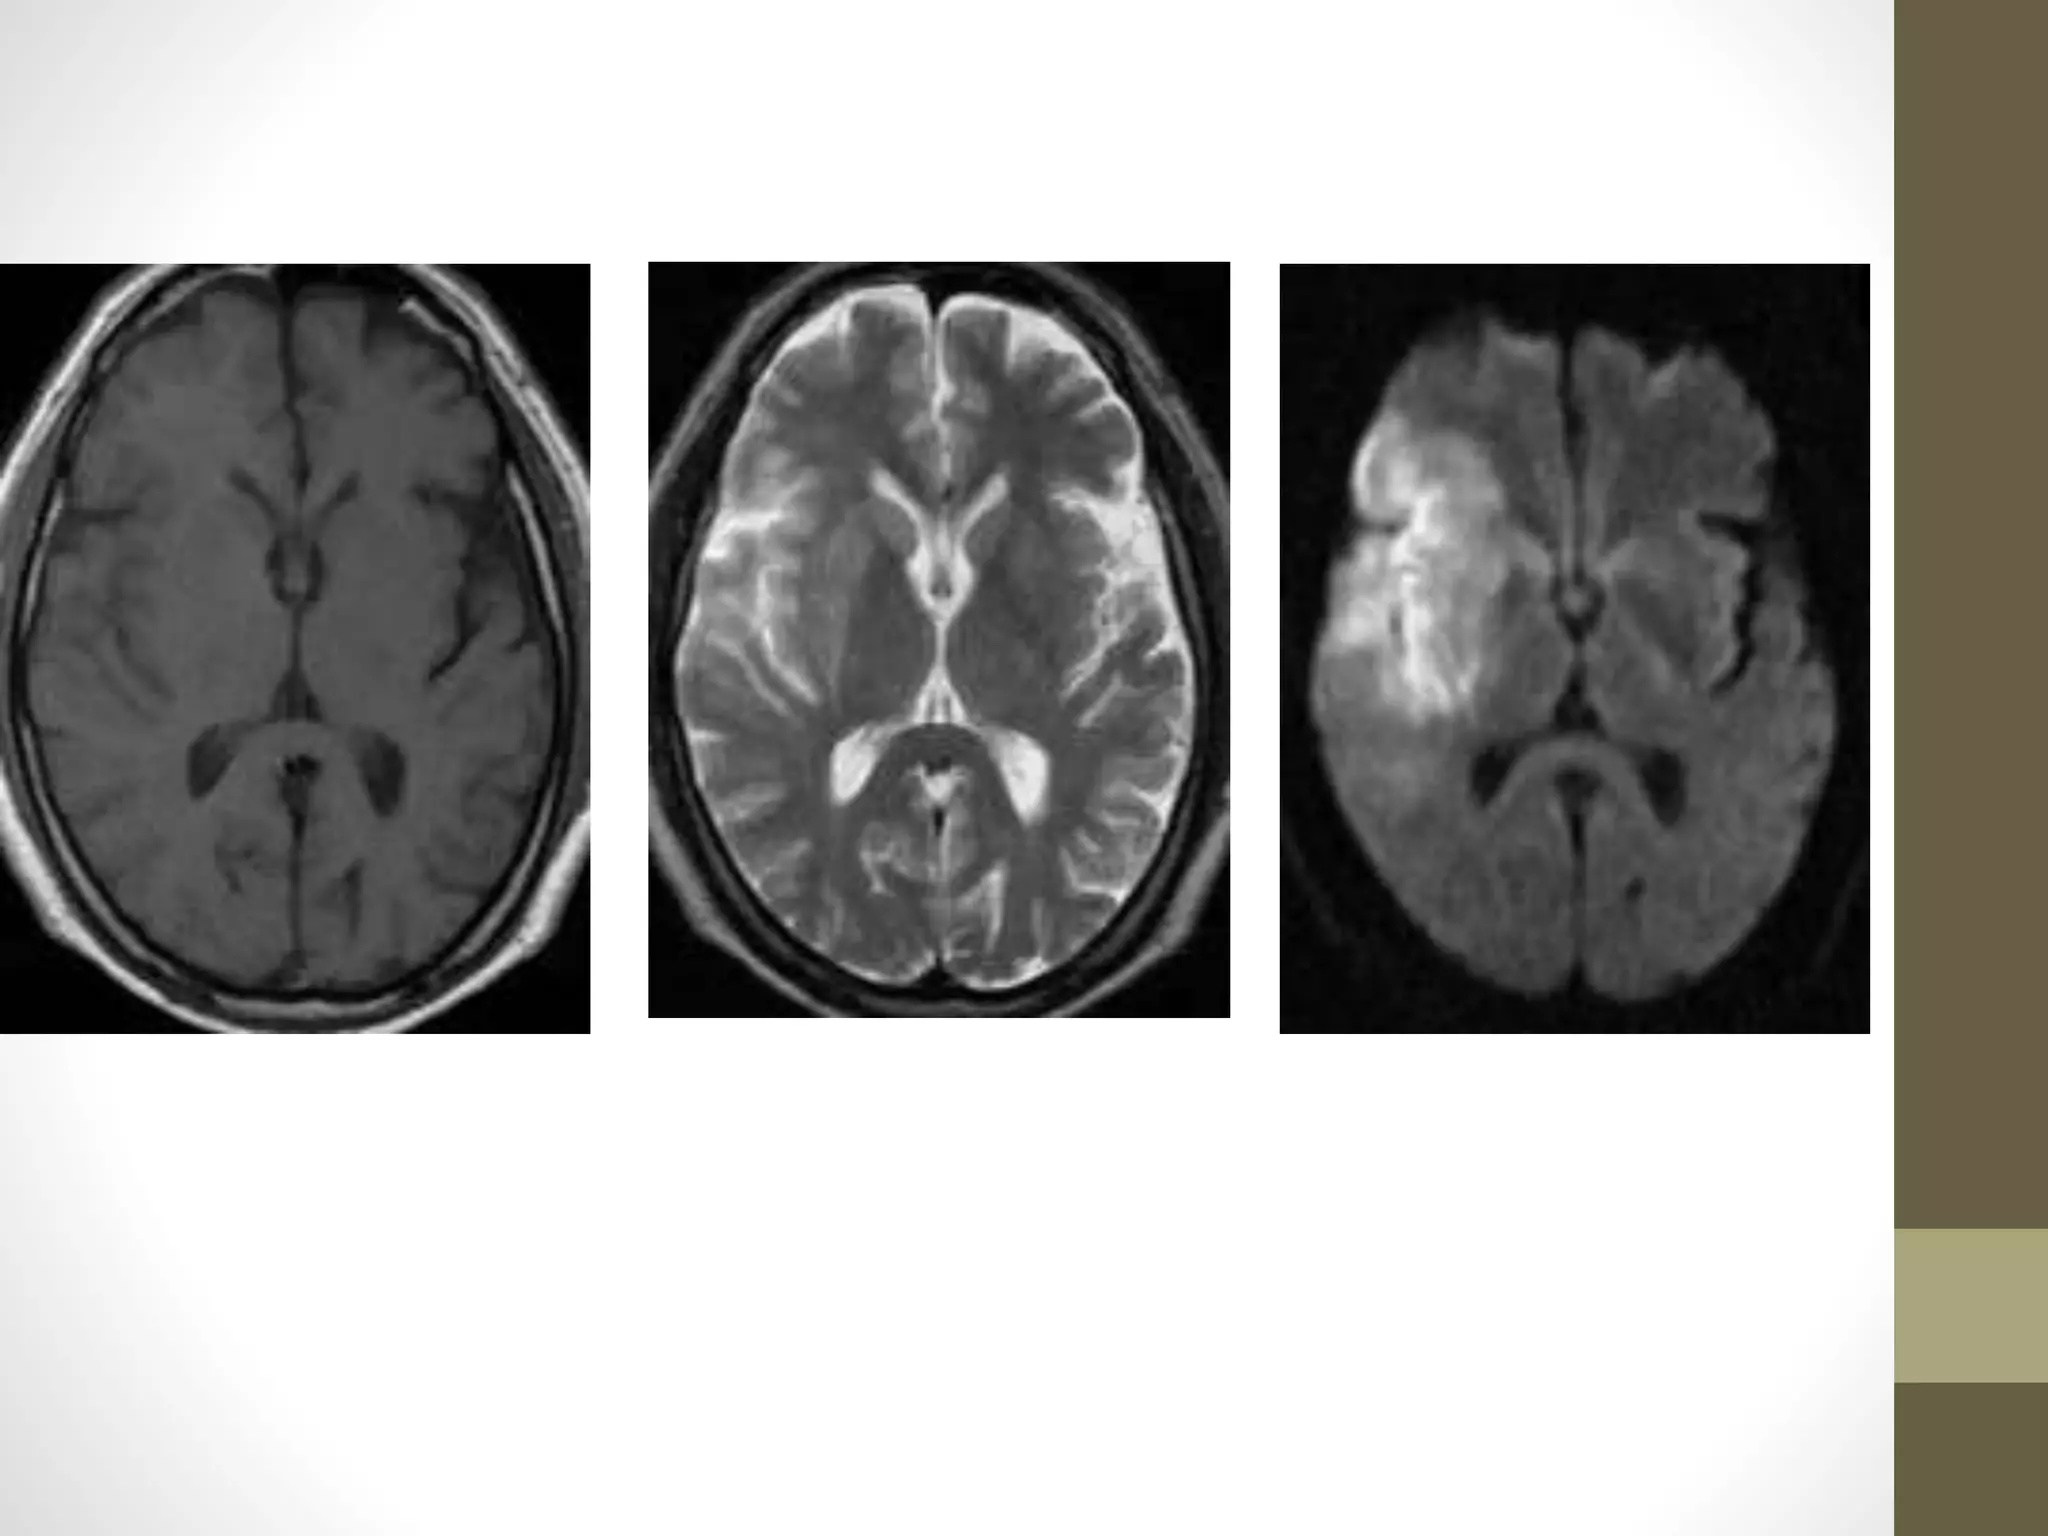

Acute

Subacute

Chronic infarct

EvaluationofacutestrokeonDWI • The DWIand ADC maps – ischemic changes -within minutes to few hours • The signal intensity of acute stroke on DW images increase during the first week after symptom onset and decrease thereafter, but signal remains hyper intense for a long period • The ADC values decline rapidly after the onset of ischemia and subsequently increase from dark to bright 7-10 days later . • This property may be used to differentiate the lesion older than 10 days from more acute ones (Fig 2). • Chronic infarcts are characterized by elevated diffusion and appear hypo or isointense on DW images and hyperintense on ADC maps